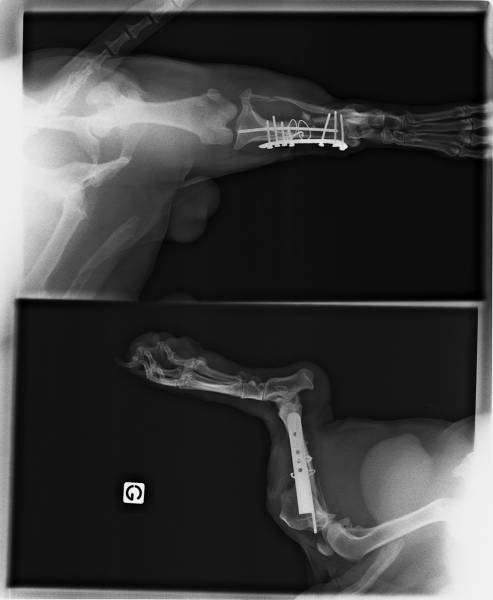

Chirurgies orthopédiques :

fractures